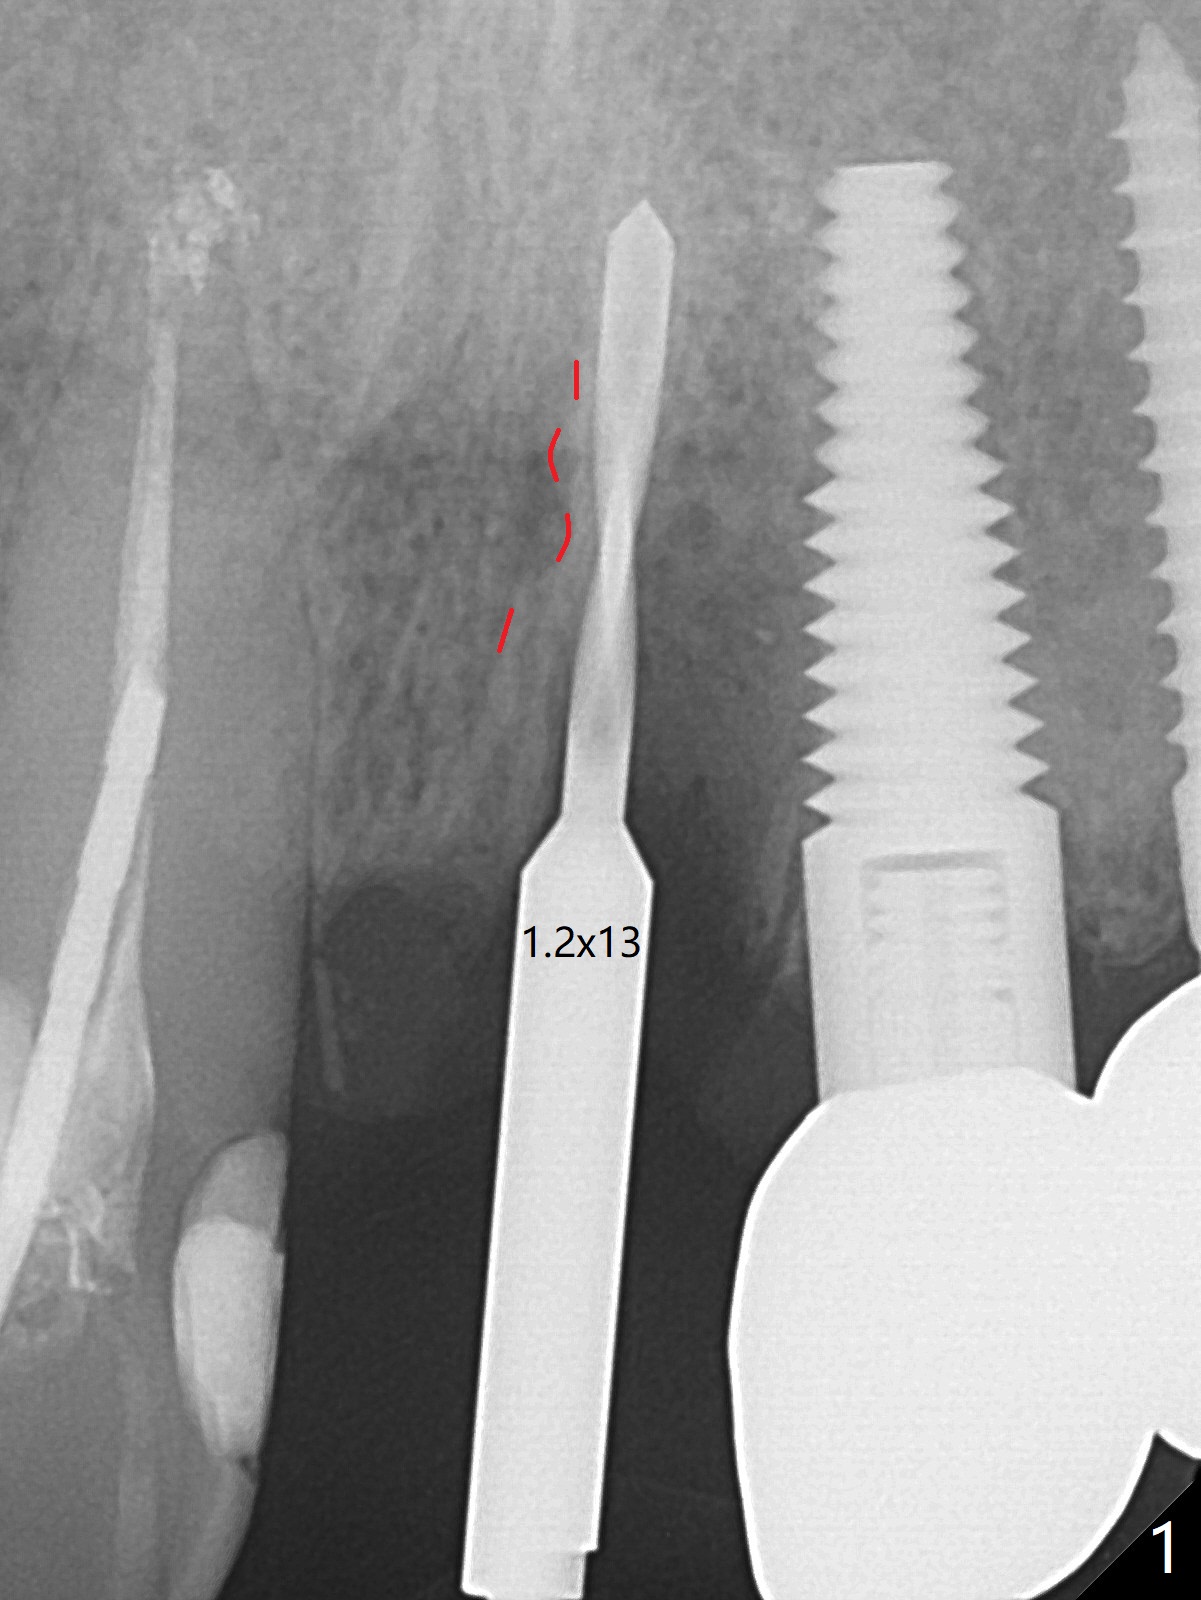

徒手种植不准确,需要反复调整,例如,为了避免接近侧切牙植体,中切牙钻洞开始于牙槽窝腭侧骨壁近中,结果接近切牙管(图一:红虚线),然后使用Lindamann bur移动钻洞,结果又太接近侧切牙(图二)。最后使用2毫米钻头试图改变钻洞方向,结果基台太接近侧切牙牙冠(图三)。而导板植入快,利索。 植入皮质骨骨粉(图四:*)后,制作临时牙冠。大约术后11天临时牙冠脱落(可能基台太短),病人没有及时复位,4天后牙槽窝愈合,可能变小,牙冠就位有些困难,造成颊侧牙龈发白(图五)。一周后牙冠又脱落,衬里后(图六:*)颊侧牙龈又显得饱满。